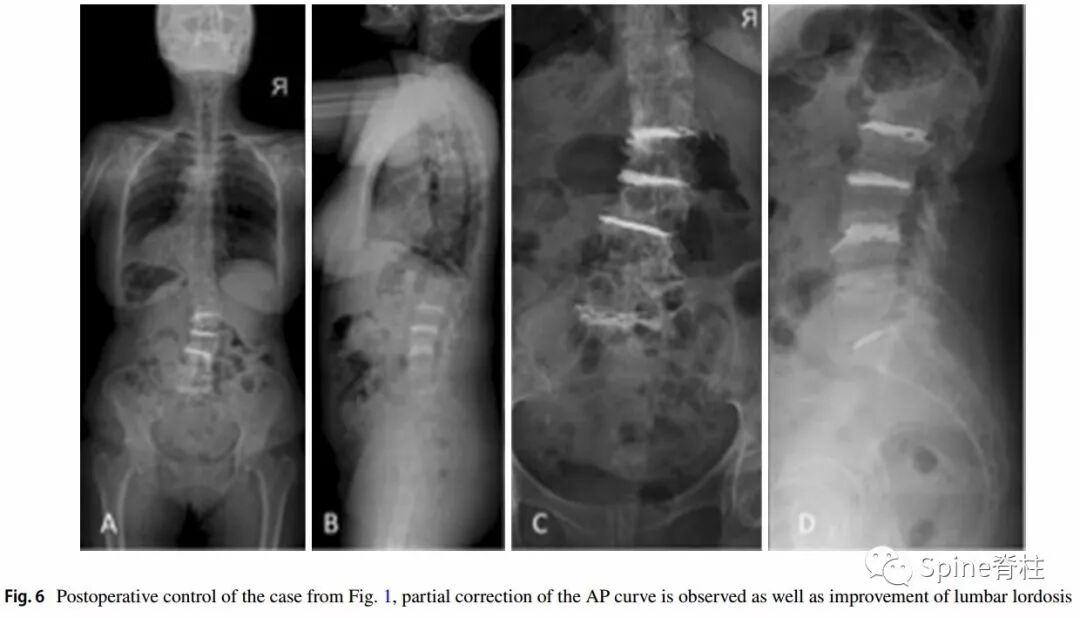

随后,P.P. Varga团队又进行了一项研究,发表在2019年的Eur Spine J上。

他们发现,PCD治疗严重腰椎间盘退行性疾病引起的轴性腰痛和功能障碍是一种有效的微创方法。同时,术后可以纠正腰椎畸形,并达到椎间孔的间接减压的效果。尤其适合于不易行开放手术的老年患者。

-

术后骶骨倾斜角和骨盆倾斜角明显减小,腰椎节段性和整体后凸、椎间盘和椎间孔高度都明显增加。VAS和ODI评分明显改善,且腰痛的改善余节段性侧凸矫正明显相关,且无明显并发症发生。

术后情况

2例退变性侧凸患者术后比较